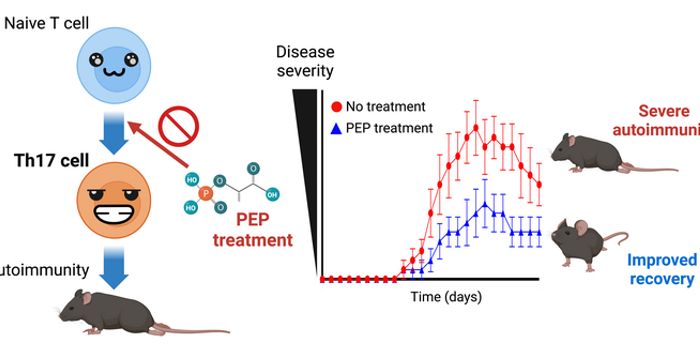

FEB 02, 2024Genetics & GenomicsMillions of people have autoimmune diseases, such as multiple sclerosis or rheumatoid arthritis but it's estim ...

DEC 28, 2023ImmunologyThe immune system regulates homeostasis by attacking foreign bacteria, viruses, and other infections. Different immune c ...